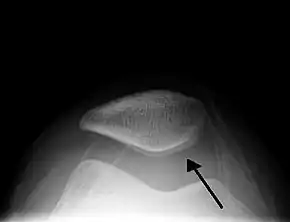

Skyline view of the patella demonstrating a large joint effusion as marked by the arrow.